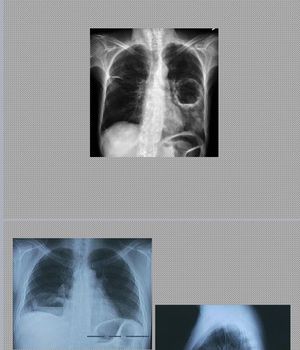

Diagnosis??

No it is lung abscess

Lung absses